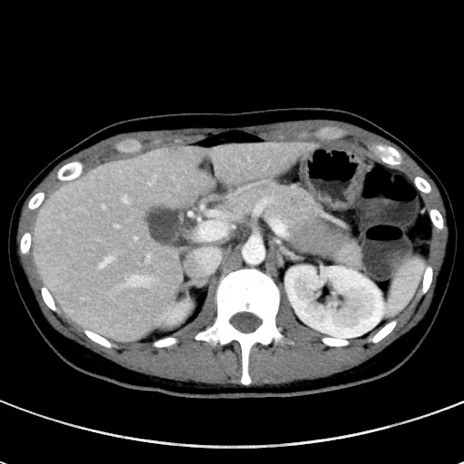

症例17(横断像)

【症例】20歳代女性

【主訴】嘔吐、下腹部痛

【現病歴】昨日夕食後に嘔吐し下腹部痛が出現。本日になっても嘔吐持続し改善しないため来院。

【身体所見】意識清明、BT 37.2℃、BP 108/67mmHg、腹部:平坦、やや硬、下腹部正中から右にかけて圧痛あり、反跳痛軽度あり、tapping pain(+)。

【データ】WBC 13600、CRP 14.94

冠状断像